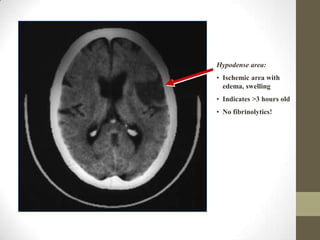

Hypodense area:Ischemic area with edema, swelling

Indicates >3 hours old

No fibrinolytics!(White areas indicate hyperdensity = blood)Large left frontalintracerebral hemorrhage.Intraventricularbleeding is also presentNo fibrinolytics!

Hypodense area:Ischemic areawith edema, swelling

• 131.

• 132.

No fibrinolytics!(White areasindicate hyperdensity = blood)Large left frontalintracerebral hemorrhage.Intraventricularbleeding is also presentNo fibrinolytics!